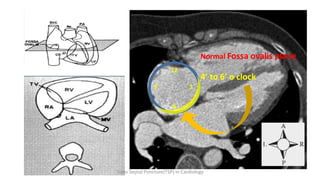

Normal Fossa ovalis plane

4’ to 6’ o clock

Trans Septal Puncture(TSP) in Cardiology